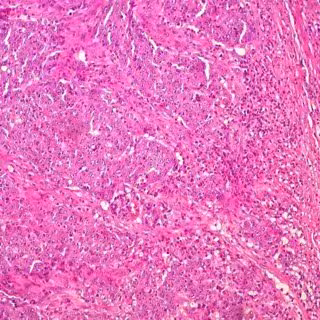

Cáncer de colon

Cáncer de colon - UCM - Archivo

Hasta ahora, numerosos estudios epidemiológicos han demostrado la asociación de la deficiencia en vitamina D con una mayor incidencia y mortalidad de diversos cánceres, como es el caso del cáncer colorrectal (CRC). La alteración de estas células troncales ("madre" o stem) es crucial en el inicio, progresión y resistencia al tratamiento del CRC. Los investigadores describen la acción del calcitriol en la células frenando la proliferación e induciendo la diferenciación de las células stem cancerosas (Cancer Stem Cells).